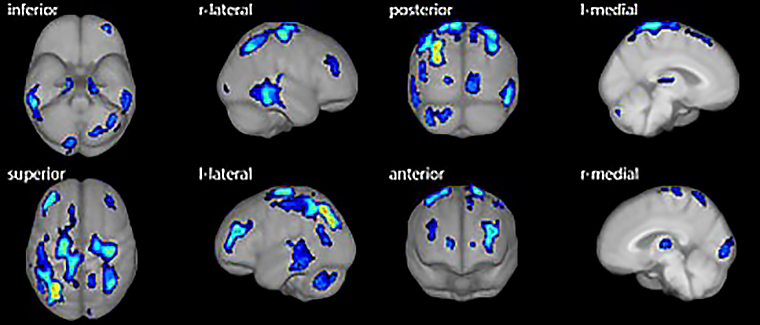

▲阿茲海默症患者腦部八向表面投影影像,藉由多角度分析可突顯異常血流分布區域,輔助醫師精準判讀。(圖/亞東醫院提供)

核醫科功能性分子影像能反映失智症病程早期的細微生理變化,是這套智慧判讀系統的核心。亞東醫院核子醫學科主任汪姍瑩醫師分享,AI系統可在資料導入後快速生成半定量Z-score分析報告與三維定位圖,輔助臨床醫師精準辨識腦區血流異常。臨床驗證結果顯示,AI判讀與專家結果一致性高達9成以上,證明人工智慧已成功融入診斷流程。

隨著全球阿茲海默症抗體藥物(如樂意保 Lecanemab 與 Donanemab 欣智樂)取得重大進展,早期確診的需求顯著增加。針對類澱粉蛋白沉積及神經纖維糾結的分子影像正子檢查,因而受到更大重視。這套AI影像分析技術能提前偵測血流異常,協助醫師「更早看見細微的變化」,提供及早確診與治療契機。